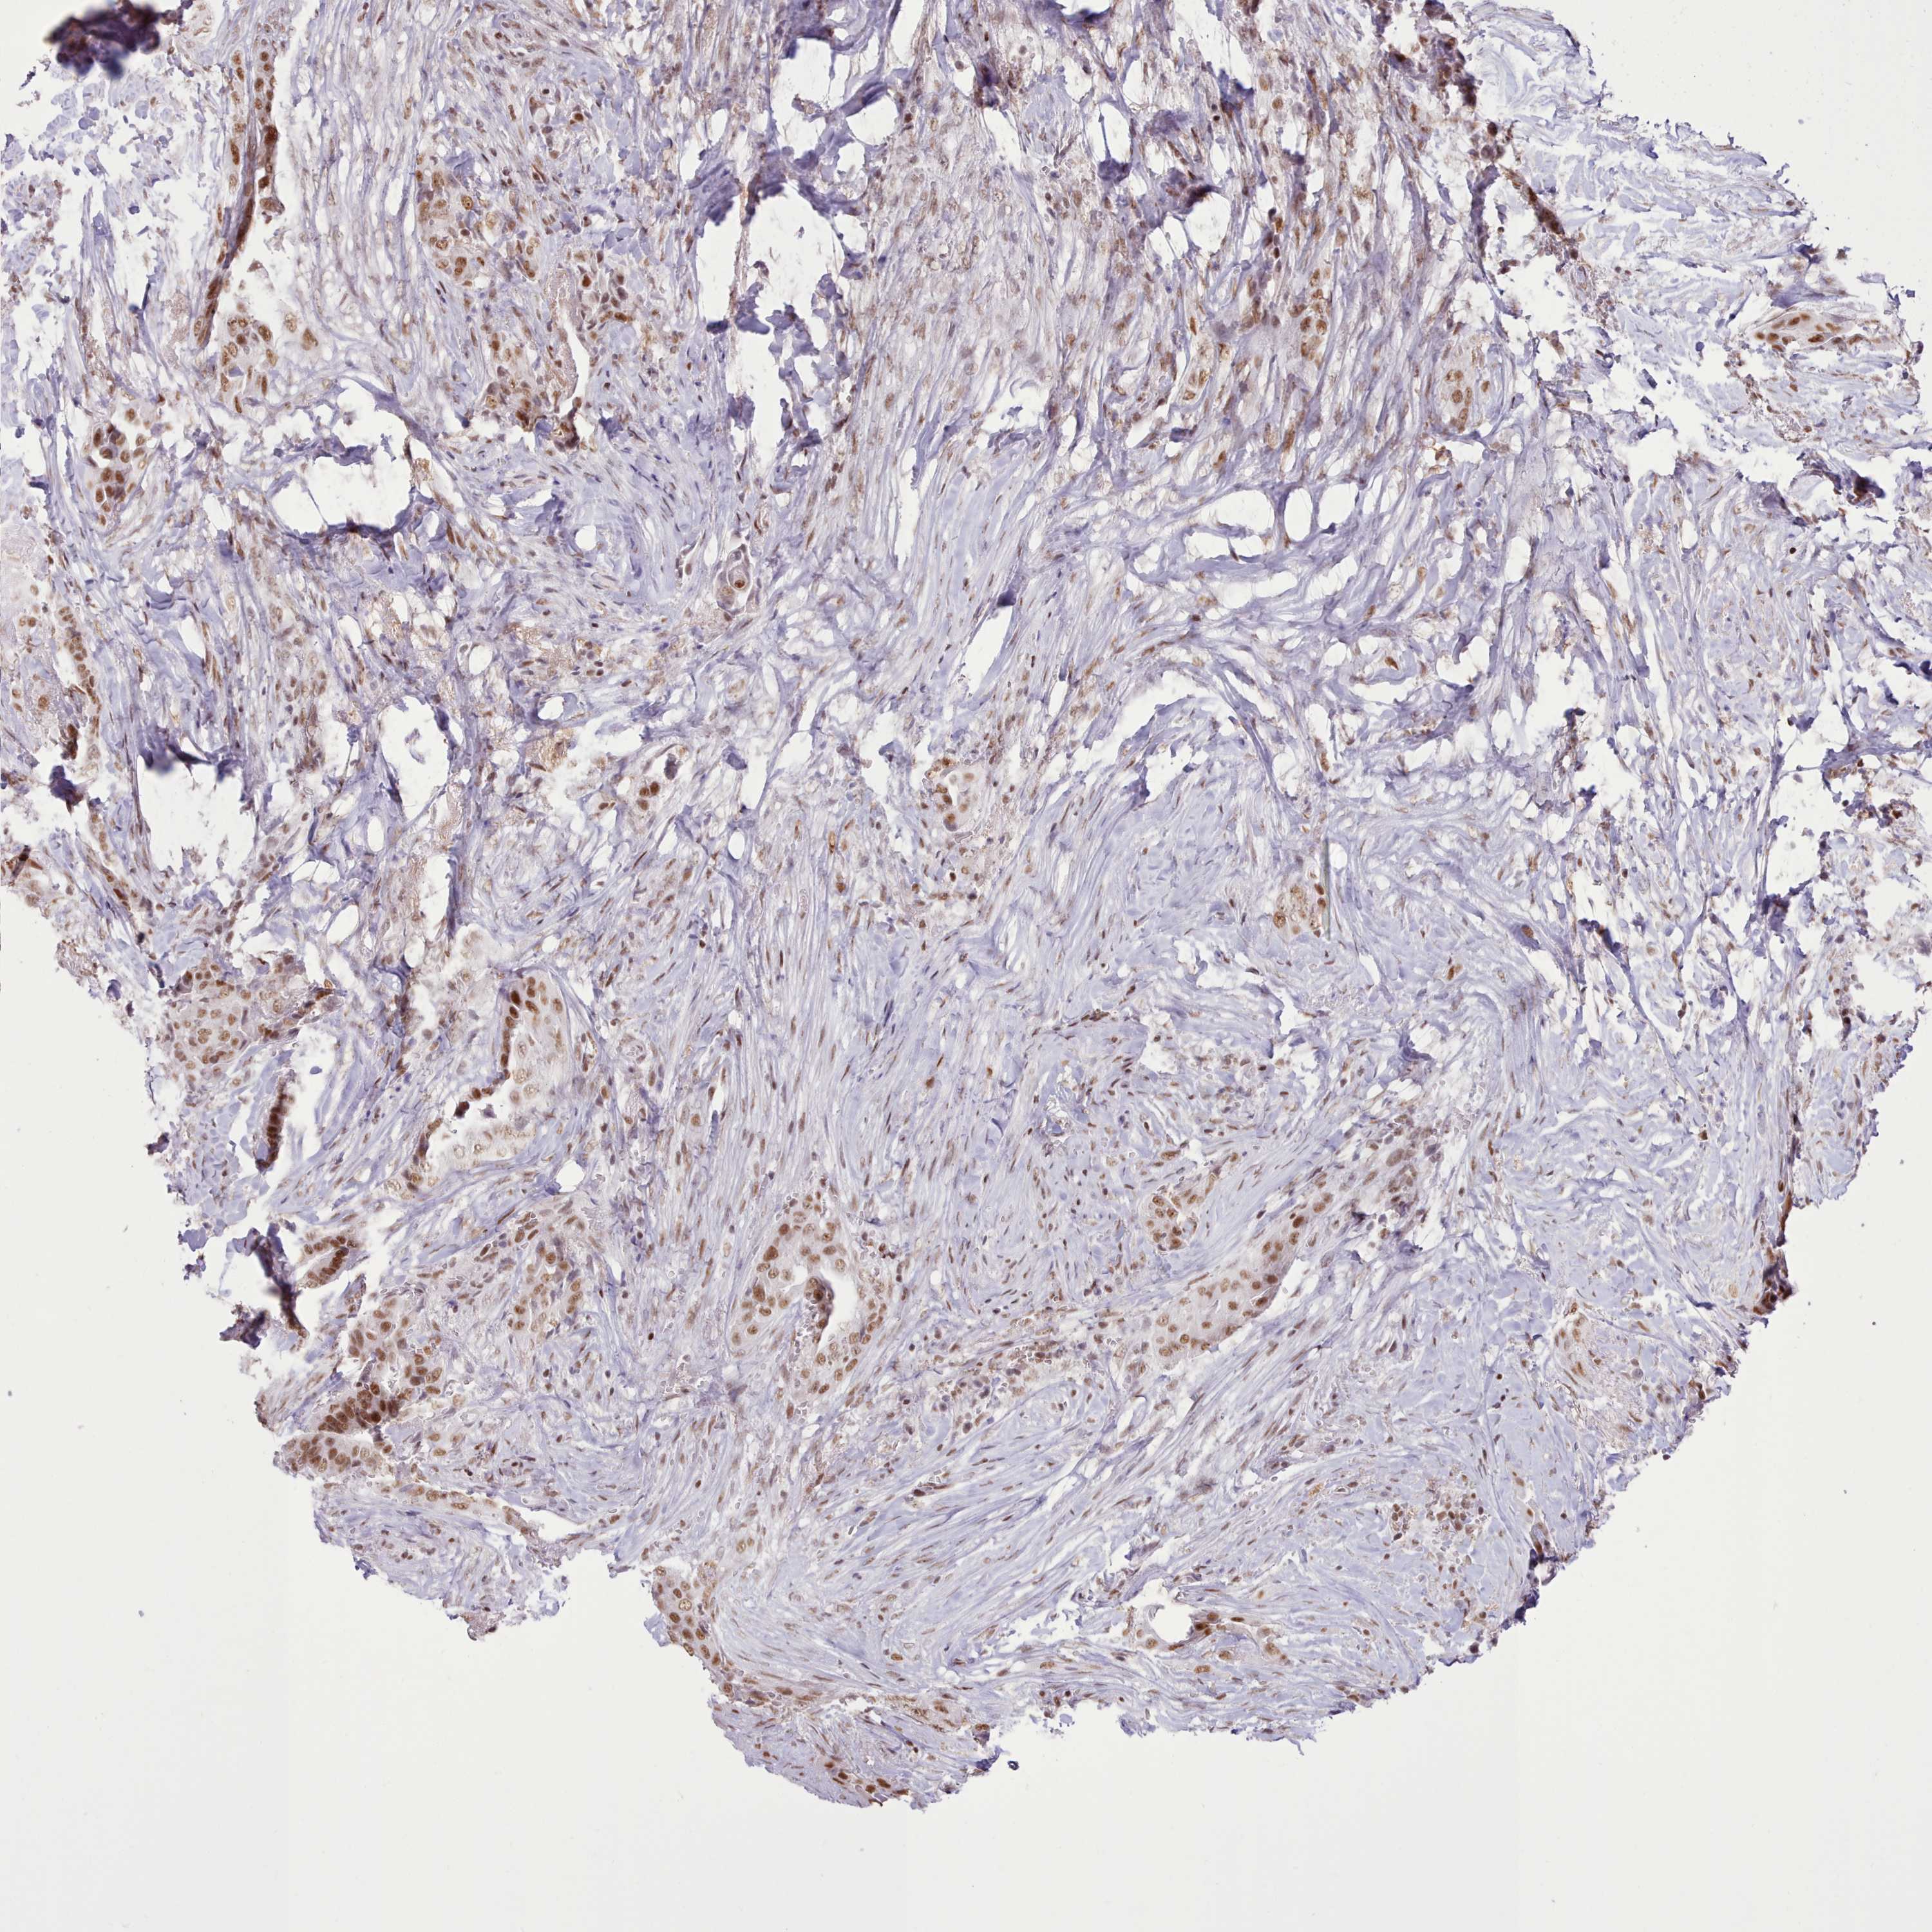

THYROID CANCER - Protein expressioni

A mouse-over function shows sample information and annotation data. Click on an image to view it in a full screen mode. Samples can be filtered based on level of antibody staining by selecting one or several of the following categories: high, medium, low and not detected. The assay and annotation is described here.

Note that samples used for immunohistochemistry by the Human Protein Atlas do not correspond to samples in the TCGA dataset.

Antibody stainingi

Antibody staining in the annotated cell types in the current human tissue is reported as not detected, low, medium, or high, based on conventional immunohistochemistry profiling in selected tissues. This score is based on the combination of the staining intensity and fraction of stained cells.

Each image is clickable and will lead to virtual microscopy that enables deeper exploration of all samples and also displays staining intensity scores, fraction scores and subcellular localization as well as patient and tissue information for each sample.

Antibody HPA052059

Staining

High

Medium

Low

Not detected

Intensity

Strong

Moderate

Weak

Negative

Quantity

>75%

75%-25%

<25%

None

Location

Nuclear

Cytoplasmic/membranous

Cytoplasmic/membranous,nuclear

Papillary adenocarcinoma, NOS